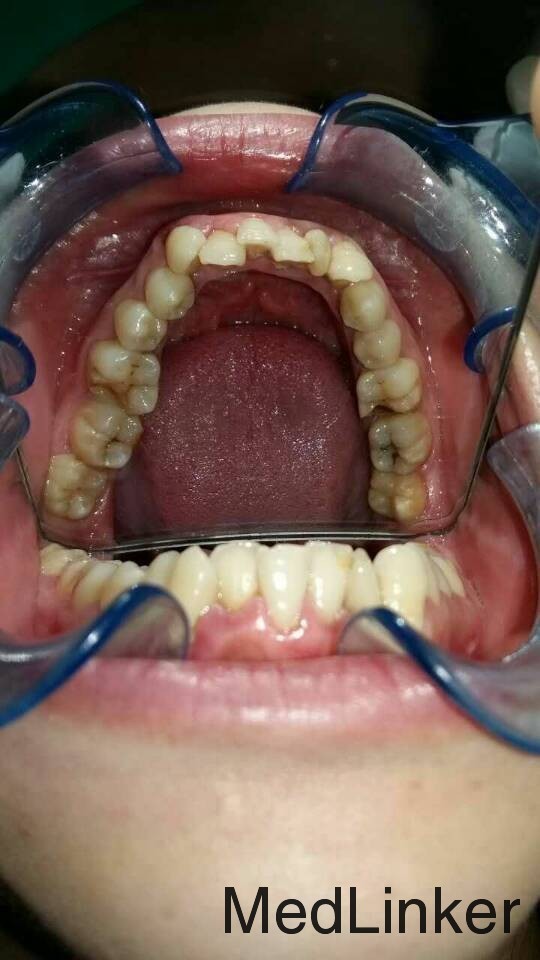

矫正一例

女,15岁,要求矫正